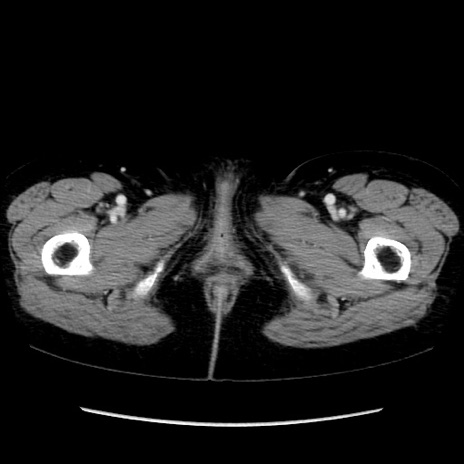

症例32(横断像)

【症例】40歳代 女性

【主訴】上腹部痛、嘔気・嘔吐

【現病歴】約9時間前頃から急に上腹部痛、嘔気、嘔吐が出現。改善しないため救急要請。

【既往歴】子宮頚癌(広汎子宮全摘術、放射線療法)、腸閉塞

【身体所見】腹部:平坦、軟、腸雑音亢進、上腹部を中心に腹部全体に圧痛あり。

【データ】WBC 8400、CRP 0.03